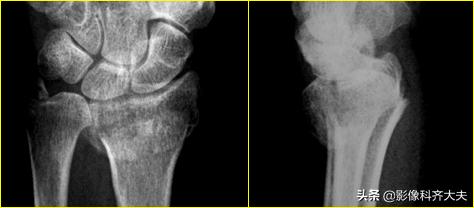

骺离骨折:儿童多见;外力经骺板达干骺端;骺线增宽;骨骺与干骺端对位异常;骨骺与干骺端一并撕脱

Colles骨折:伸展型桡骨远端骨折,在桡骨远端2-3cm以内的横行或粉碎骨折,远侧向桡或背侧移位,常合并尺骨茎突骨折。